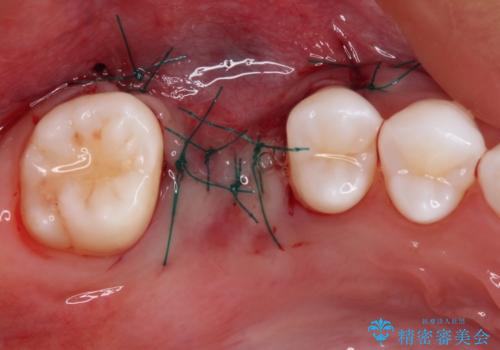

抜歯前のCTにより、インプラントを埋入するために必要な歯槽骨量が不足することが予想されたため、サイナスソケットリフトにより上顎洞内の粘膜を挙上して、インプラントを埋入することとしました。

その後は、オールセラミッククラウンにて補綴することとしました。

仮歯装着中に頻繁に脱離したため、オールセラミッククラウンは脱離の少ないスクリュータイプとしました。